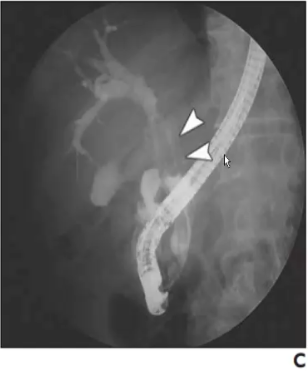

❖ IPNB典型表现为扩张胆管腔内边界清晰的乳头状肿块或绒毛状软组织影

❖ 增强实性部分动脉期明显强化,门脉期及延迟期呈等或稍低密度

❖ MRCP肝内胆管局部囊状扩张,内见结节状充盈缺损上下游胆管明显扩张

❖ IV型:局灶囊性扩张伴乳头状肿块